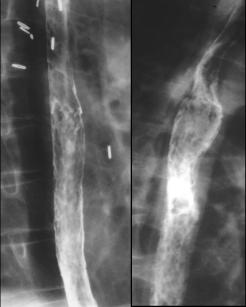

4 Oesophagite radique : Apparaissant 6 mois

apres l'irradiation , sourtout si association avec chimio

therapie par adriamycine . Lesion stenosant en segmetaire

avec lesion ulceree au region expose au champ de irradiation

.

Oesophagite radique forme chronique : Stenose

segmentaire au champ expose d'irradiation |

Varice oesophagien :

Diagnostic par endoscopie , TOGD et CT scanner . Image

endoscopique de varice est specifique , aspect de varicose .

Image radiologique TOGD de varice est l'epaisissement

des plis de l'oesophage , image en chaine de bijoux ou des

sangsues et aspect serpengineuse sur CT

scanner :